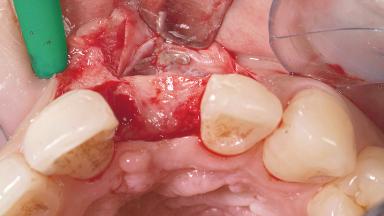

A 30-year-old female patient had lost tooth 21 and was referred to our clinic for consultation and treatment. Due to advanced apical infection, tooth 21 had been extracted two months earlier at another clinic and an acrylic-resin tooth had been bonded to the adjacent teeth. The patient desired implant treatment to avoid any damage to the adjacent natural teeth. While the patient had no history of any systemic disorder, she was a heavy smoker and exhibited medium to advanced periodontitis in the entire jaw. After the initial treatment to achieve a pocket probing depth of less than 4 mm and no bleeding on probing, a decrease in the height of the papillae mesial and distal to the extraction site and overall gingival recession were observed.